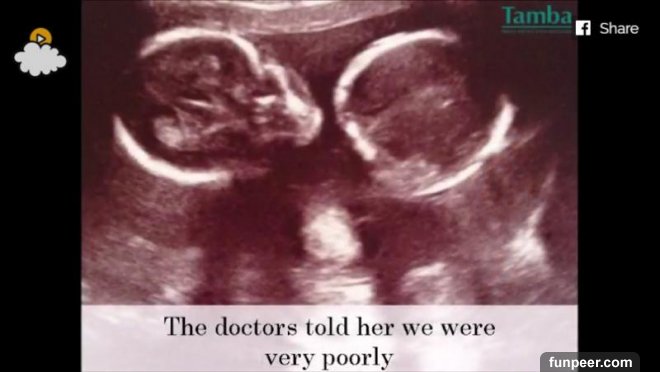

在她懷孕22週的時候她去醫院做了產檢,產檢時醫師運用新的科技拍攝到了許多清晰的畫面,甚至能夠明確地看到胎兒的樣貌,還拍到了胎兒對著鏡頭揮手,甚至拍到用腳將攝影機踢走的畫面!

這些畫面看似溫馨,但是醫生看到這個畫面卻相當震驚,因為這些舉動正是反映出兩兄弟正在努力的活下去!事實上這對雙胞胎患有輸血綜合症,這是一種發生在雙胞胎之間的,血液不成比例的並發症!

亨利從胎盤中得到的血量比較少,而賽巴斯汀則是得到的血太多,導致心臟造成負擔!

這個雙胞胎輸血綜合症的發生率約在10-15%,如果沒有接受治療的話,亨利和賽巴斯汀基本上一定會死!就算進行手術,也有相當高的機率導致兩人都無法存活!

而這些照片也被倫敦的聖喬治醫院雙胞胎專家BaskyThilaganathan所拍下的,他準備要這對雙胞胎進行「雷射燒蝕手術」,這對許多雙胞胎患有同樣症狀的人來說,這多半是他們能夠看小孩的最後一面。